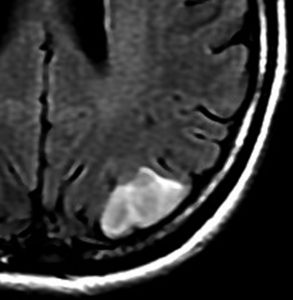

• 初期には、一つの脳回に限局して境界が明瞭な小さな腫瘍として発見されることもあります (single gyrus glioma)

フレア画像です。左上前頭回の星細胞腫ですが,境界がとてもはっきりしていて限局性 localized single gyrus glioma です。びまん性 diffuseには見えません。IDH1の変異があり,1p/19qの欠失はないので星細胞腫グレード2です。上の例とは全く違う臨床像を示しますが,分子病理でも区別はつきません。頑張って早めに全摘出して治してしまった方がいいタイプです。再発を避けるために,supratotal resectionと言って,周囲の正常脳組織も10mmくらい余分に摘出します。